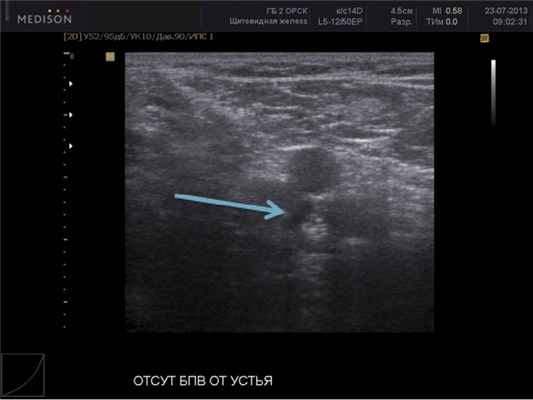

В 20,0% случаев (n=30) наблюдали обструкцию вены. В зависимости от степени поражения стенки выделены два типа обструкции — тотальная и сегментарная. В случае тотальной обструкции, которая встретилась у 9,3% (n=14) пациентов, происходит полное исчезновение вены (рис. 3). В ряде случаев возникает сегментарная обструкция сосуда: в 6 случаях на верхних конечностях, в 10 случаях на нижних конечностях.

Рис. 3. Ультразвуковая сканограмма области сафенофеморального соустья при обструкции большой подкожной вены.